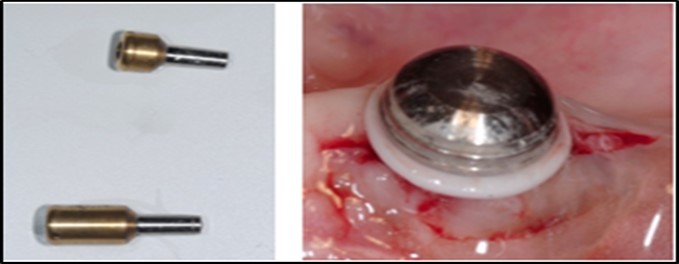

Post operatively after 3 months, osseointegration was evaluated clinically and radiographically (Figure 5a,b) and the implants were well prepared to receive the prosthesis. The second stage surgery was performed in which cover screws were removed and healing abutment were inserted into the implants (Figure 6). After a time period of two weeks, peri-implant soft tissue healing was examined, and existing denture was relined after relieving at the abutment site. Later, the healing abutment is removed using a 1.25 mm hex driver. Internal portion of the implant is irrigated and dried to make sure if it is free of debris and soft tissue. A periodontal probe was used to measure the gingival cuff height at the right and left canine site of implant location. Selected ball abutment were placed onto each implant using 1.25 mm hex driver and 30 Ncm torque wrench (Figure 7A).

Figure 7.(A) View of 2.0mm and 5.0mm post Locator Abutments with a 2.0mm post. (B) Placement of the Locator Abutment after the well of implant has been cleaned with alcohol on a cotton-tipped applicator.

A transferable mark with an indelible pencil is placed on top of each ball abutment and old denture is seated to ideally determine the location for attachment housings. It is followed by preparation of recesses in the intaglio surface of the denture to accommodate the housings (Figure 7B). Lingual vent holes are made for escape of excess acrylic. Placement of nylon processing insert into each of the housings is done with insert seating tool. Figure 8 Seating of the attachment housing onto each ball type abutment is done (Figure 9). Undercuts are blocked out under the housing and soft tissue to prevent acrylic resin from locking the denture onto the abutment. Application of self curing acrylic is done into recessed area and around titanium housings for bonding of the housings to denture. Insertion of denture was done and guiding the patient into proper occlusion with the opposing arch. After the curing of acrylic, denture is removed. Excess acrylic is removed around the housings and lingual vent hole later it is polished (Figure 10). Replace nylon retention insert instead of processing insert into the housings. The insert must seat securely in place and be in level with the housings rim. Overdenture is seated over the ball abutments (Figure 11). Proper instructions have been given to the patient on insertion and removal of prosthesis (Figure 12). The patient was recalled at 1 week, 3 weeks, 3 months, 6 months follow up appointments.

According to the literature, it appears that “interarch space required for the retention of a prosthesis to the implant (distance from the shoulder of the implant to the incisal edge) is about 12 to 14 mm as follows: a thickness of 2–3 mm of soft tissue is generally present above the implant, an area of 2 mm from the lining of the edentulous ridge to the bar needs to be present for suitable cleaning 15, 4.5 mm bar thickness, 2 mm for the acrylic resin and the rider 21 and 3 mm for the teeth” 22. Most attachment systems with staples include height of the matrix and the abutment, ranging between 5–6 mm 23. (Figure 7A,B,) In conclusion, patients with well-preserved ridge, who have lost teeth due to caries benefit from reduced interarch space for an implant overdenture. In addition to this, the space often limited interferes with the reinforcement of the prosthesis making it hard for the dentist to use the space required for devices such as staple systems 23. “Thinning the soft tissue during the surgical act and the use of internal connection to implants can help us overcome the problem of limited vertical space” 22.